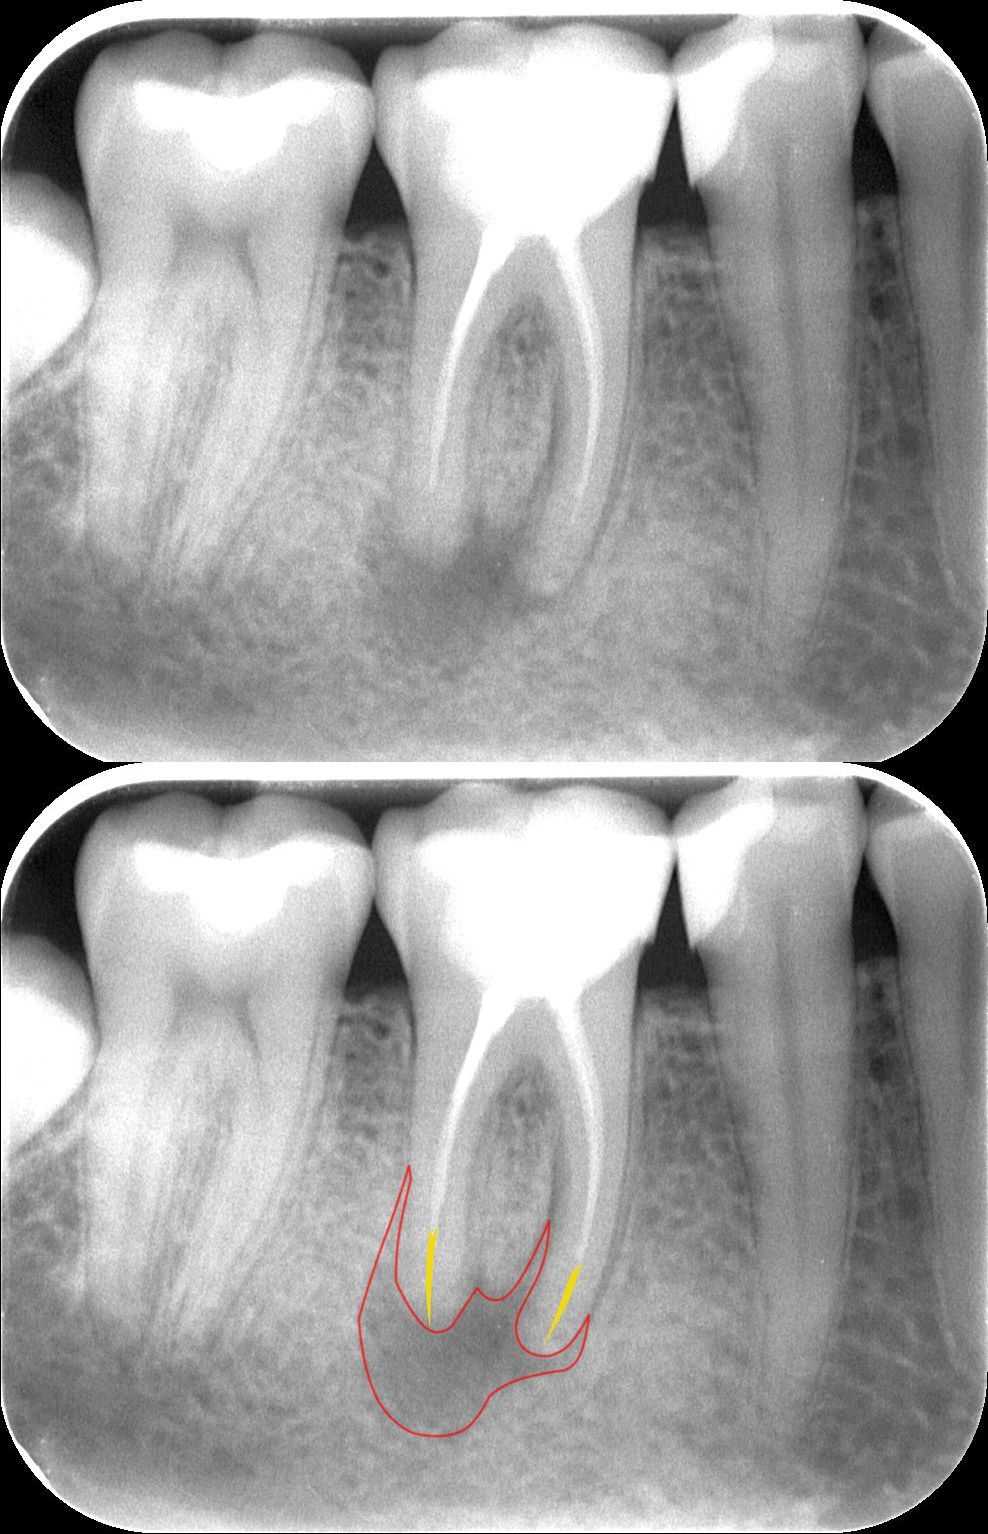

A teljes, kész gyökértömés, illetve az üvegszálas csap beragasztása után készült a felvétel. A csapos megerősítésre sajnos azért volt szükség, mert a fog koronájának jó része hiányzott. Ilyenkor a maradék foganyag védelme érdekében vagy öntött, vagy üvegszálas csapot helyezünk a fogba.

mikroszkópos gyökérkezelés 4. kép

3 hónapos kontrollfelvétel. A gyógyulás még nem teljes, de már egyértelműen látható a kedvező folyamat. A kiinduló képen megfigyelhető, hogy a gyökércsúcsok körül lévő elváltozás, az a jellegzetes fekete árnyék már halványodik, a gyulladás helyét egyre jobban az ép csont tölti ki.

mikroszkópos gyökérkezelés 5. kép